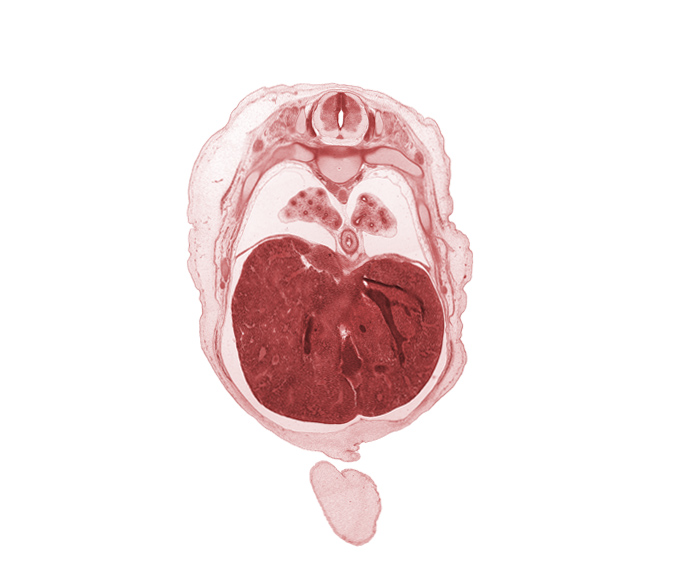

Carnegie Embryo #462 | Location: 4-01-01

Keywords: T-6 spinal ganglion, aorta, azygos vein, cephalic edge of umbilical cord, ductus venosus, efferent hepatic vein, inferior vena cava (hepatic part), liver prominence, lower lobe of left lung, lower lobe of right lung, muscular layer of esophagus, neural arch, osteogenic layer, rib 8, rib 9, subarachnoid space, surface ectoderm, sympathetic trunk

Source: The Virtual Human Embryo.